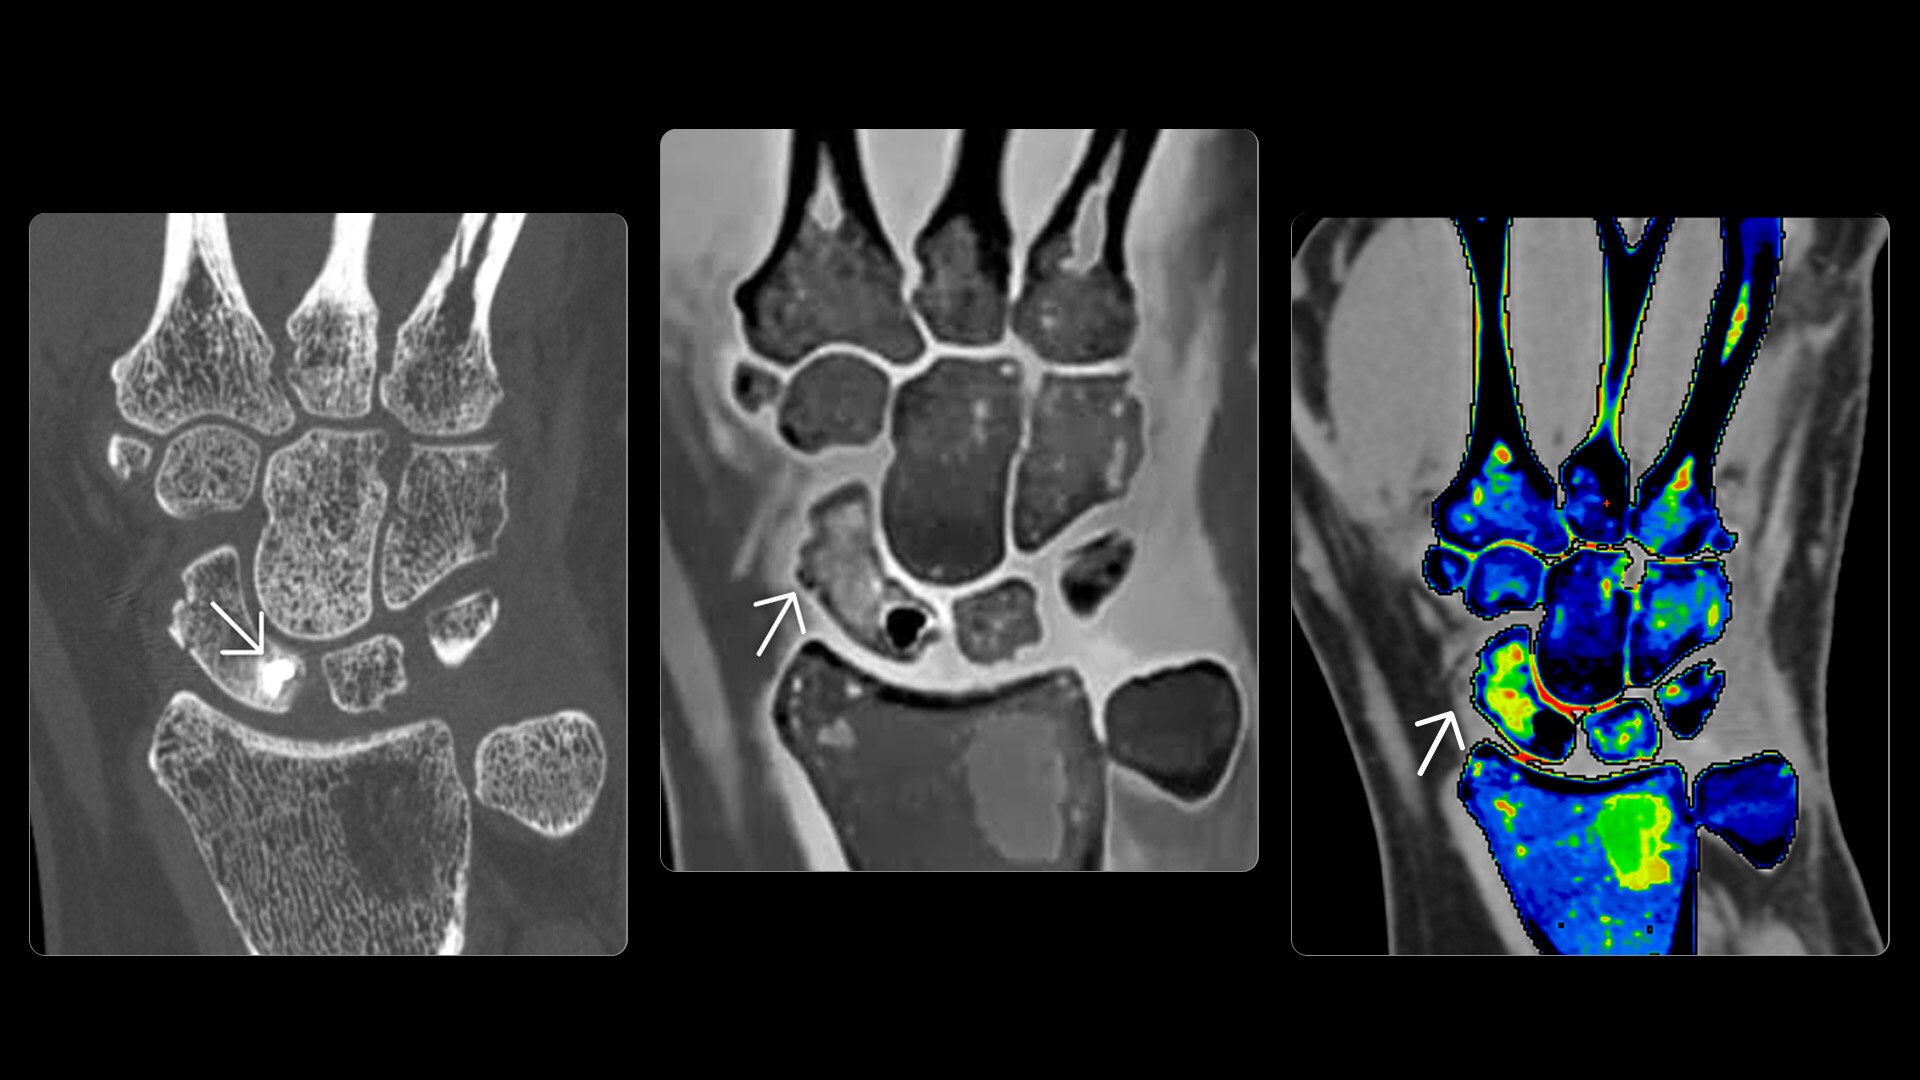

On-demand spectral imaging enabled by 8-energy bins

Our advanced spectral imaging capabilities are intended to allow you to experience the difference between seeing and knowing so you can confidently detect, characterize and monitor disease.

Photonova Spectra is also designed to enhance material separation for tissue characterization and disease quantification, bringing potentially greater diagnostic confidence in every acquisition across care areas.

A full range of spectral imaging series is generated natively on console and available for transfer to PACS. The full-fidelity spectral data acquisition is intended to provide native DICOM images and material maps to support clinical diagnosis, with improvements of up to 4x enhanced energy discretization1, 2x higher material map spatial resolution2, and 2x improved iodine detectability3.